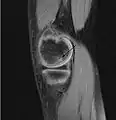

Magnetic resonance imaging (MRI) is useful for staging OCD lesions, evaluating the integrity of the joint surface, and distinguishing normal variants of bone formation from OCD by showing bone and cartilage edema in the area of the irregularity. MRI provides information regarding features of the articular cartilage and bone under the cartilage, including edema, fractures, fluid interfaces, articular surface integrity, and fragment displacement.[37][38] A low T1 and high T2 signal at the fragment interface is seen in active lesions. This indicates an unstable lesion or recent microfractures.[30] While MRI and arthroscopy have a close correlation, X-ray films tend to be less inductive of similar MRI results.[38]

Sagittal MRI: Linear low T1 signal at the articular surfaces of the lateral aspects of the medial condyle of the femur confirms the presence of OCD.